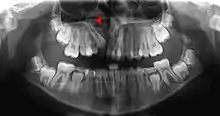

Alveolar process

The alveolar process (/ælˈviːələr, ˌælviˈoʊlər, ˈælviələr/)[1] or alveolar bone is the thickened ridge of bone that contains the tooth sockets on the jaw bones (in humans, the maxilla and the mandible).[2] The structures are covered by gums as part of the oral cavity.

.jpg.webp)